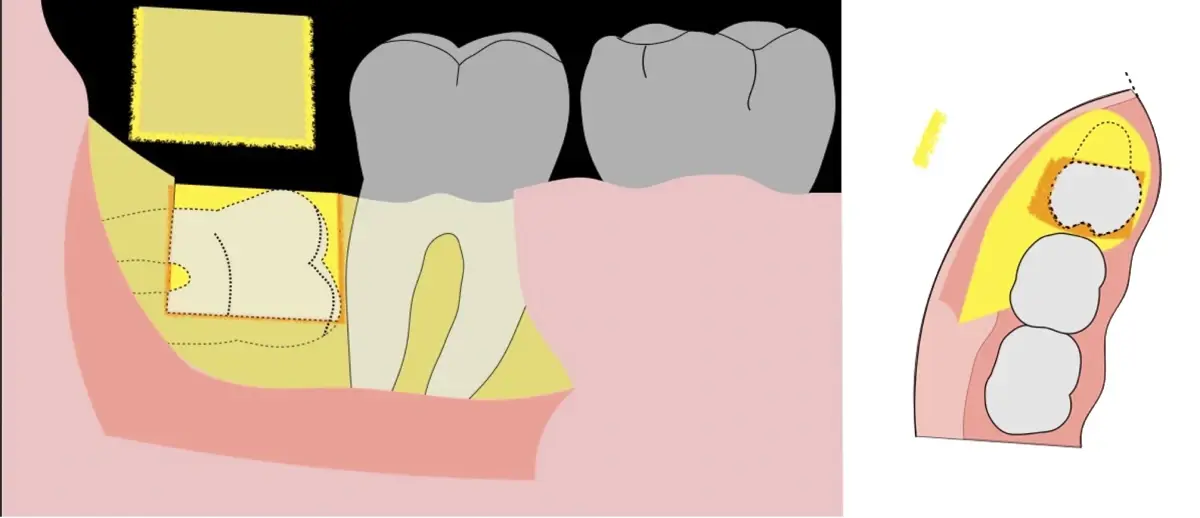

Figura 4. Demarcación de la zona de osteotomía con insertos de corte recto y/o angulado a nivel oclusal. Vista frontal (a). Vista oclusal (b).

Figura 5. Fractura y eliminación oclusal del fragmento óseo de la porción coronal oclusal.

Figura 6. Demarcación y fractura de la zona de osteotomía a nivel vestibular con inserto aserrado recto y/o angulado.

Figura 7. Eliminación del fragmento vestibular.